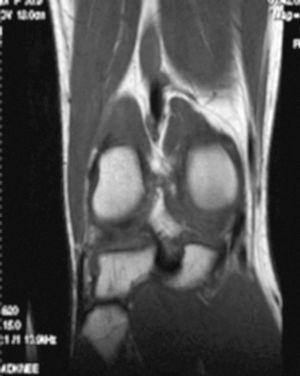

L'RM mostra (figs. 1, 3 i 5):

Figura 1 RM. Imatge potenciada en T2 amb supressió de greix. Cossos lliures en recessió articular interna.